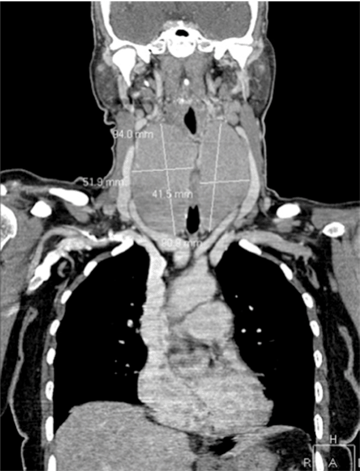

Investigations showed an elevated CA-125 558 kU/L and TSH 14 mIU/L. Full blood count, lactate dehydrogenase (LDH), renal and liver function tests were normal. HIV and syphilis serology were negative. Computed tomography (CT) scan of neck showed a massively enlarged thyroid gland with a maximum diameter of 9.4 cm (right lobe) and 9.1 cm (left lobe). (Figure 1) There was associated esophageal compression and the mass displaced the airway anteriorly without compromise. The CT scan of chest was negative for malignancy and CT scan of abdomen showed an enlarged liver and spleen as well as a central pelvic lesion extending into the abdomen (Figure 2A) causing right hydronephrosis and hydroureter. (Figure 2B)

Figure 1: Coronal computed tomography of the chest and neck prior to chemotherapy showing massively enlarged thyroid with airway displacement. The right thyroid lobe measures 94x52 mm and the left measures 91x42 mm.